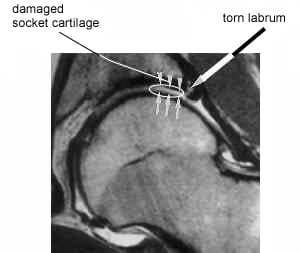

MRI of a hip with a torn labrum

When the extra bone on the femoral head and/or neck hits the rim of the acetabulum, the cartilage and labrum that line the acetabulum can be damaged.

The extra bone can appear on X-rays as a seemingly very small “bump.” However, when the bump repeatedly rubs against the cartilage and labrum (which serve to cushion the impact between the ball and socket), the cartilage and labrum can fray or tear, resulting in pain. As more cartilage and labrum is lost, the bone of the femur will impact with the bone of the pelvis. This “bone on bone” notion is most commonly known as arthritis.

Tears of the labrum can also fold into the joint space, further restricting motion of the hip and causing additional pain. This is similar to what occurs in the knee of someone with a meniscus tear.